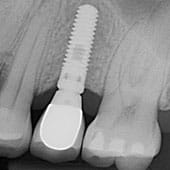

Un implante dental, es un aditamento hecho de Titanio, que actúa como sustituto de las raíces de los dientes perdidos. Se colocan en el interior del hueso, llegándose a integrar en el de una forma totalmente natural con el resto de los tejidos de la boca. A continuación, y sobre el implante, se confecciona el nuevo diente artificial, el cual va atornillado a este. (Corona implanto-soportada)

Gracias a un proceso biológico llamado osteointegración descrito hace ya más de 50 años por el profesor Branemark, el implante se sujeta al hueso. Una vez formada dicha integración es cuando el implante puede soportar la nueva prótesis o diente artificial.

Una vez colocado el implante se deberá esperar un tiempo, para que el propio hueso del paciente crezca alrededor del implante, gracias a un proceso biológico llamado osteointegración descrito hace ya más de 50 años por el profesor Branemark, el implante se sujeta al hueso. Una vez formada dicha integración es cuando el implante puede soportar la nueva prótesis o diente artificial.

Una vez transcurrido el tiempo necesario para la cura del implante, se procederá a tomar unas impresiones de su boca, para confeccionar el diente que irá sobre el implante.